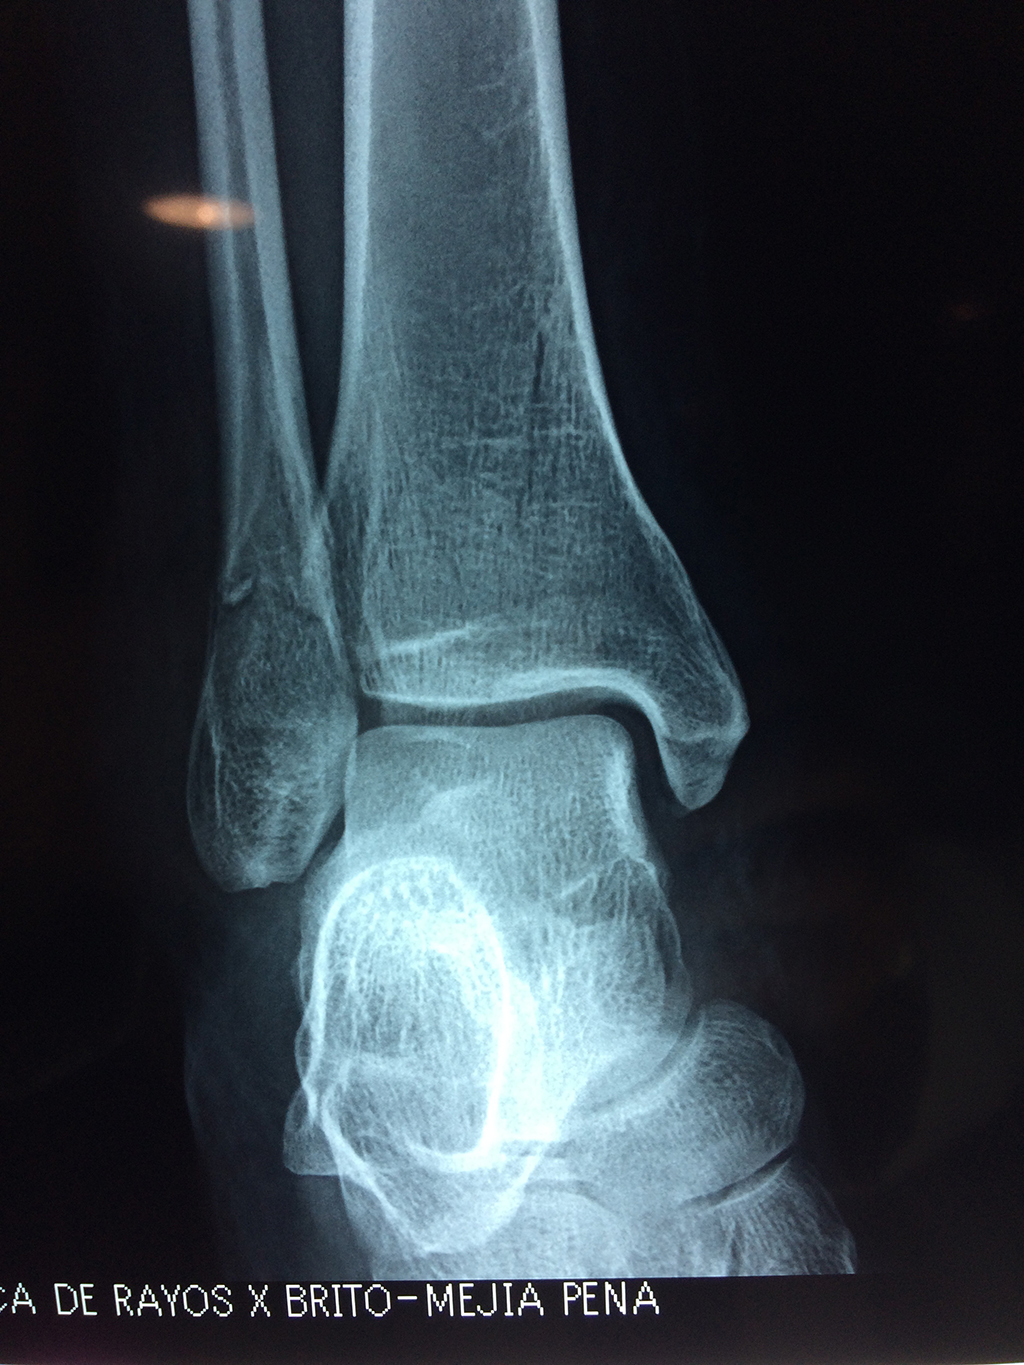

Una fractura de tobillo es la rotura de uno o más de los huesos del tobillo. Estas fracturas pueden ser:

- Parciales (el hueso está sólo parcialmente fisurado, no del todo).

- Completas (el hueso está perforado y está en 2 partes).

- Producirse en uno o ambos lados del tobillo.

- Los extremos de los huesos están desalineados entre sí (desplazados).

- La fractura se extiende hasta la articulación del tobillo (fractura intra-articular).

- Los tendones o ligamentos (tejidos que sujetan los músculos y los huesos entre sí) están rotos.